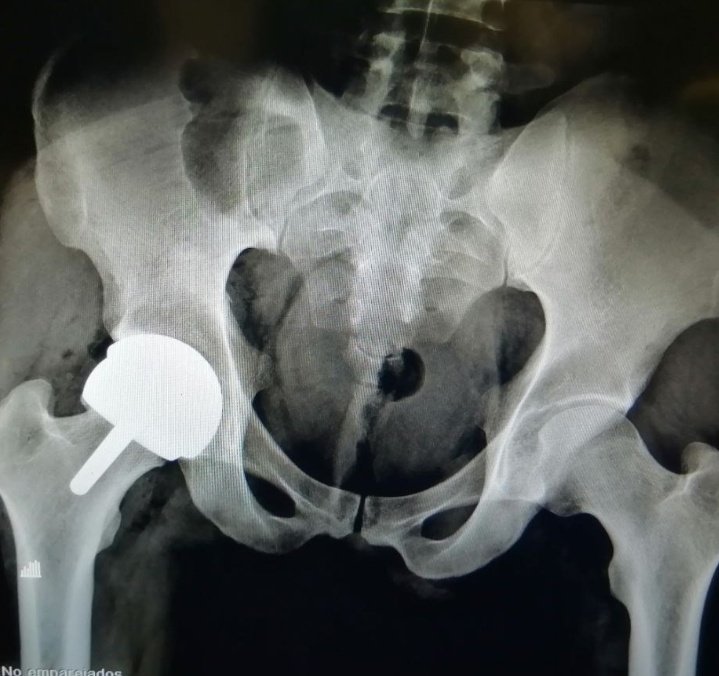

29 yo Male Right Hip ON Total Hip RESURFACING #recons #orthotwitter #adultrecons @caderarodilla #DrDarioGarin Tboughts @DrLeeRubin @hugortopedista @generalorthomd When arthroscopy? When arthroplasty?

RPURATA's tweet image. 29 yo Male

Right Hip ON

Total Hip RESURFACING

When arthroscopy?

When arthroplasty?